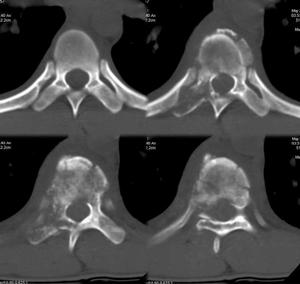

對被懷疑為類癌綜合徵的病人,可做化驗室檢查如粗篩實驗、尿中5-HIAA測定、腫瘤組織中5-HT測定。套用B超、CT\MRCI以及ERCP等定位檢查技術,為制定手術方案提供診斷資料。

套用B超、CT、MRI以及ERCP等檢查,有助於了解胰島細胞類癌的部位、大小和數目,為制訂手術方案提供定位診斷資料。